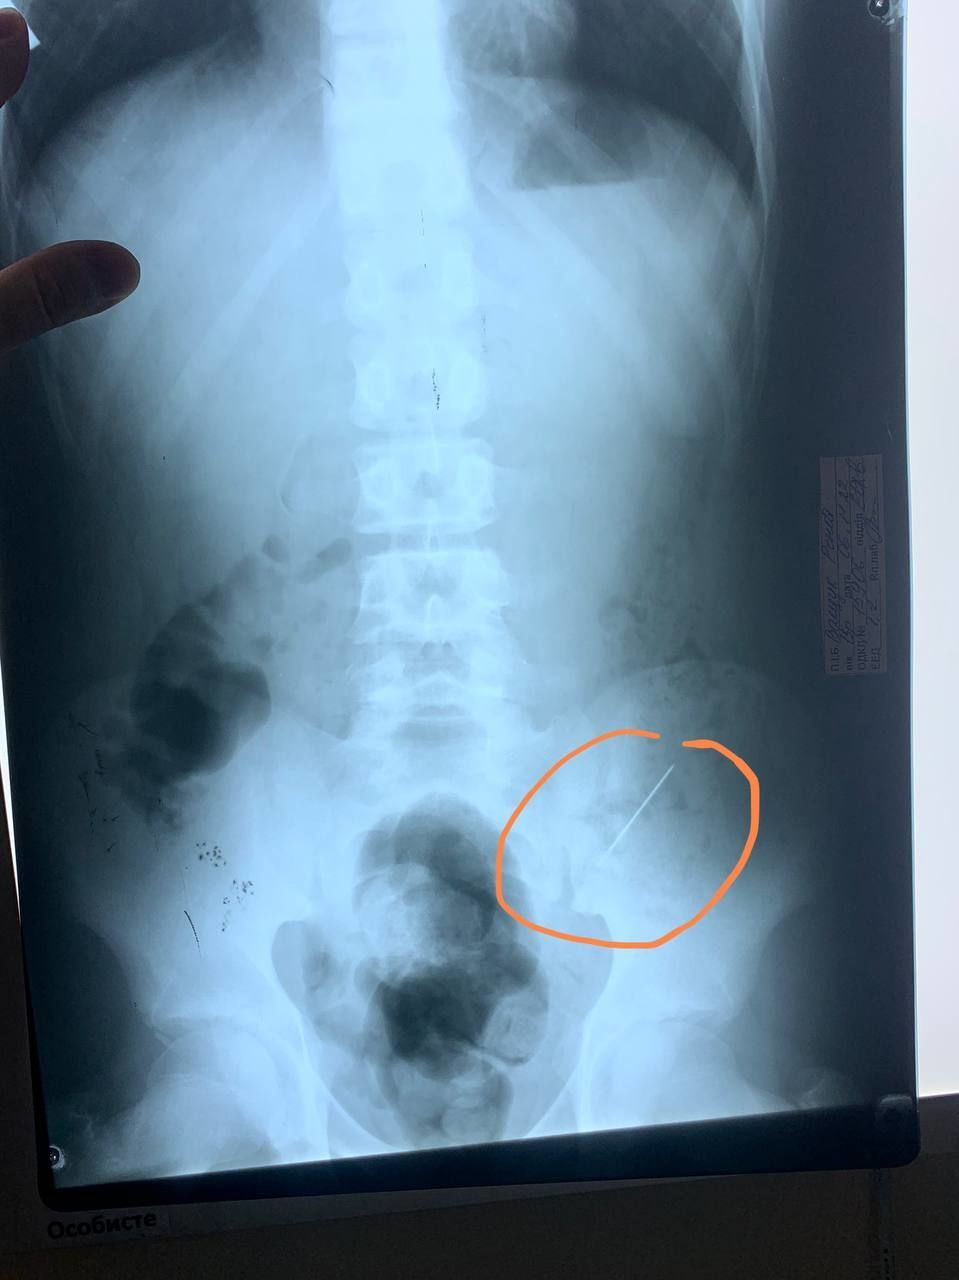

У Дніпрі 13-річний хлопець випадково проковтнув голку. Перелякані батьки привезли дитину до лікарні, де її врятували хірурги.

Пацієнту оперативно зробили рентген, після чого ситуація могла отримати кілька варіантів розвитку – гастроскопія або ж оперативне втручання, якщо голка пошкодить внутрішні органи, розповіли в Регіональному медичному центрі родинного здоров’я.

“Втім наші хірурги передбачили менш механічний, проте й доволі ризикований варіант: постійне динамічне спостереження (пальпація живота, повторні знімки), відтак був шанс, що голка вийде сама”, – розповіли в медичному центрі.

“Та в нашому випадку на другу добу постійного спостереження лікарями, вдалося досягти хепіенду, голка вийшла природнім шляхом (на щастя) не пошкодивши жодного органу”, – зазначили медики.